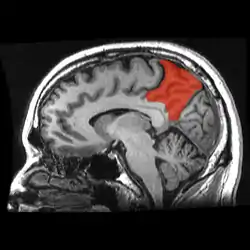

![]() Sagittal MRI slice with the precuneus shown in red. (Anterior to the left.) | |

In neuroanatomy, the precuneus is the portion of the superior parietal lobule on the medial surface of each brain hemisphere. It is located in front of the cuneus (the upper portion of the occipital lobe). The precuneus is bounded in front by the marginal branch of the cingulate sulcus, at the rear by the parieto-occipital sulcus, and underneath by the subparietal sulcus. It is involved with episodic memory, visuospatial processing, reflections upon self, and aspects of consciousness.

The precuneus is located on the inside between the two cerebral hemispheres in the rear region between the somatosensory cortex and forward of the cuneus (which contains the visual cortex). It is above the posterior cingulate. Following Korbinian Brodmann it has traditionally been considered a homogeneous structure and with limited distinction between it and the neighboring posterior cingulate area. Brodmann mapped it as the medial continuation of lateral parietal area 7.